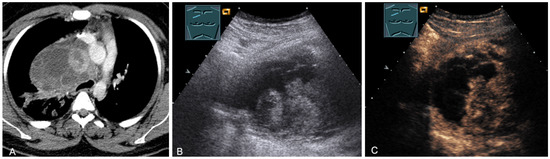

The spectrum of primary mediastinal masses includes a heterogeneous group of benign and malignant pathologies [28,31,36]. Benign primary mediastinal masses include congenital cysts (Figure 14), lipomas, thyroid tissue (Figure 15), benign thymomas, thymic residues, scar tissue, ganglioneuromas (Figure 16), schwannomas (Figure 17), and giant cell tumors (Figure 18) [28,31,36].

Figure 14.

A cystic mediastinal mass on CT (provided by Prof. Dr. Andreas H. Mahnken, Marburg, Germany) (A), B-mode US (B), and CEUS (C), surgically confirmed as a mediastinally located bronchogenic cyst.